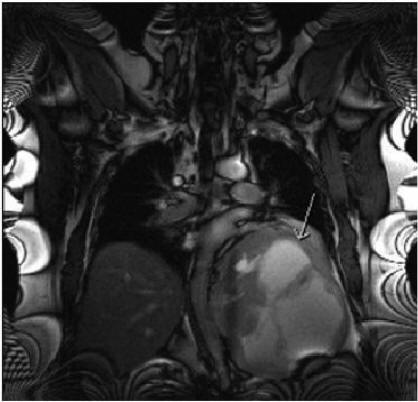

Mass Per Abdomen: A Diagnostic Dilemma - Jaypee Journals

With difficulty to walk and pain in the left hip. Patient presented with left lower limb DVT after the first cycle of chemotherapy with paclitaxel Mass Per Abdomen: A Diagnostic Dilemma Journal of South Asian Federation of Obstetrics and Gynaecology, ... Retrieve Content